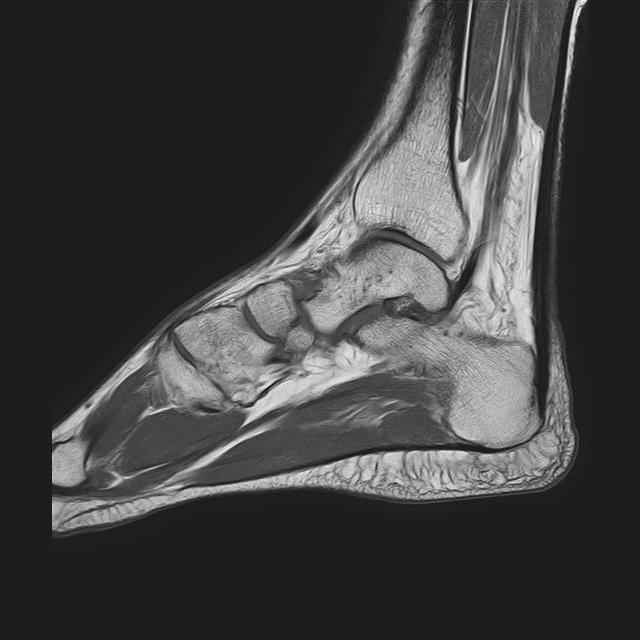

Мужчина 36 лет, пострадал около 8 месяцев назад в ДТП (водитель мотоцикла).

Подтаранный вывих лечили гипсовой лонгетой. Недиагностированным остался перелом ладьевидной кости, который беспокоит в настоящее время. Аваскулярный некроз кости, похоже.